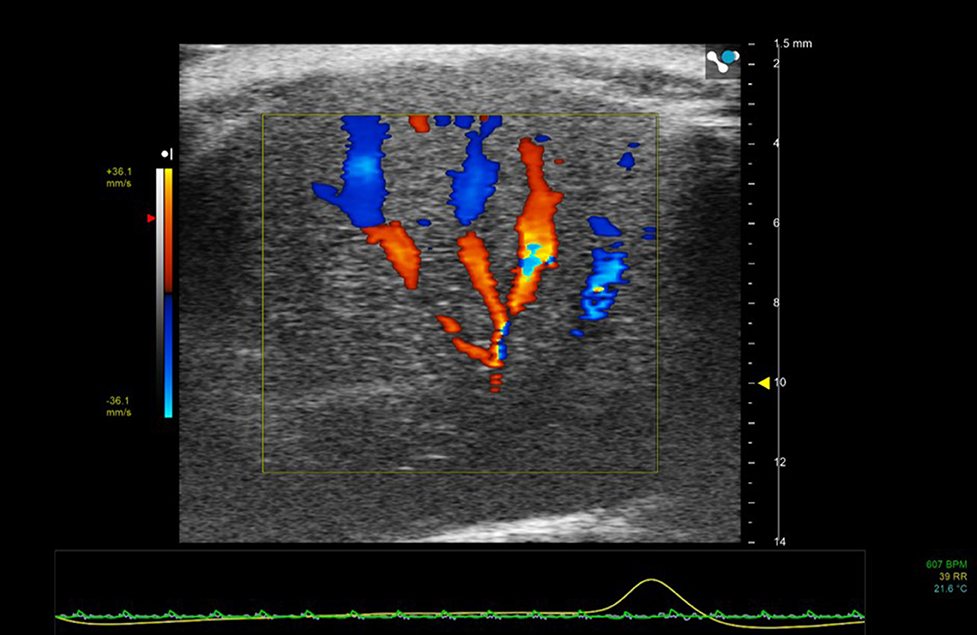

Color Doppler

In Color Doppler mode, the mean velocity of scatterers (red blood cells) within a pre-selected region-of-interest are color-encoded and superimposed on the gray-scale B-mode image. In clinical applications blood moving away from the transducer tends to be encoded in shades of blue and blood moving toward the transducer in shades of red. For preclinical applications, color Doppler is especially useful for the rapid location of vessels (Figure 5).

Figure 5. Color Doppler region of interest superimposed on 2D B-mode image of mouse liver. Color Doppler shows the vessel network—blue indicating movement of blood away from the transducer and red toward the transducer.